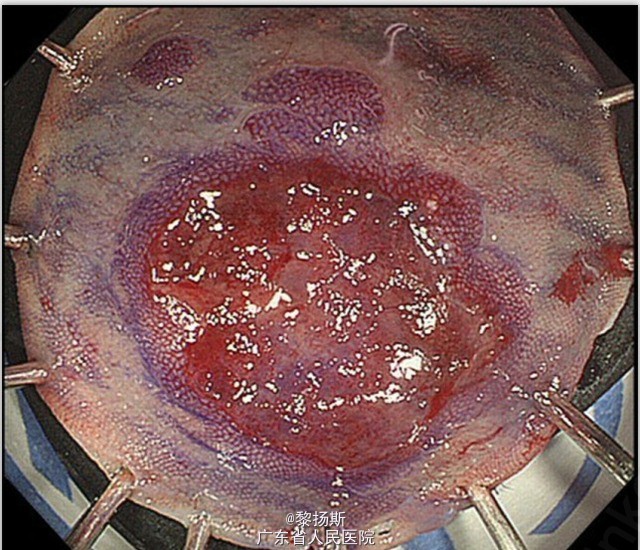

肠镜检查,横结肠见一小肿瘤而转诊至作者所在内镜中心。患者无便血、腹泻及腹痛,病史无显著异常,无大肠癌家族史。血液检查除转氨酶稍高外,其余均正常。血清 CEA、CK19 片段及 AFP 均处于正常范围。增强 CT 扫描未见淋巴结转移或远处转移。 肠镜检查,横结肠处见一略红的表浅隆起病灶(大小为 1cm)、中央略凹陷(图 1A)。窄带成像(NBI)放大,见杂乱的不规则微血管,凹陷区表面无此表现(图 1B)。色素内镜下用龙胆紫后放大观察,凹陷区可见一小灶不规则凹陷,其他区域由于存在大量粘液而未见这种凹陷。

粘膜下注入生理盐水后,病灶隆起,然后行内镜下粘膜切除术。肿物完整切除、无不良情况。 大体检查,肿瘤为 11*5mm 表浅隆起型病变,伴表浅凹陷(图 2)。将标本以 2mm 间隔连续切开。镜下,肿瘤细胞排列成梁状及巢状(图 3A、B),周边可见少许腺癌成分(图 4A)。 免疫组化检查,肿瘤主体神经内分泌标记阳性,如 CgA(图 5A)、Syn(图 5B)、CD56。两种肿瘤成分免疫组化表现类似,二者均为角蛋白 AE1/AE3(图 4B)及 CD10(图 4C)阳性,MUC2(图 4D)、MUC5AC、MUC6 及阿辛蓝阴性。非肿瘤区的粘膜内未见 CgA 阳性细胞巢。肿瘤区核分裂 >20/10HPF,Ki-67 指数 >50%。 术后诊断为神经内分泌癌,粘膜下层微浸润(300μm)、无淋巴结转移。